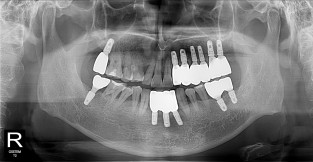

풀케이스

치료기간 : 2022-03-18 ~ 2023-09-15

1. 상기 x-ray 이미지 모두 동일한 해당 의료기관에서 진료한 환자입니다.

2. 상기 x-ray 이미지 모두 동일 인물의 것입니다.

3. 치료 전 이미지는 2022-03-18에 촬영했으며, 치료 후 이미지는 2023-09-15에 촬영하였습니다.

4. 상기 x-ray 이미지 모두 동일 조건에서 환자분의 동의를 받아촬영되었습니다.

* 임플란트 시술은 환자분의 상태(고혈압, 당뇨 등)에 따라 부작용이 있을 수 있으니, 반드시 전문의와 상담이 필요합니다.

* 임플란트 수술 부작용

: 수술 후 출혈, 교합, 통증, 붓기, 염증 등의 문제점이 발생할 수 있습니다.)